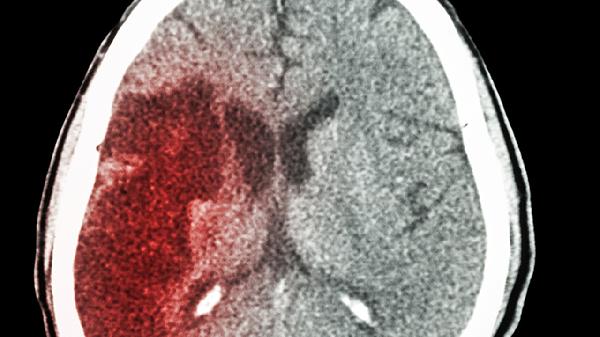

55岁大爷脑梗突发!提醒:要想脑梗远离,睡觉前这3件事千万别做

55岁的老张怎么也没想到,睡前那杯酒竟成了脑梗的导火索。医生在急诊室摇头叹息:“这个季节,像这样的病例已经接诊了第8个...”其实很多悲剧,都源于那些被忽视的睡前坏习惯。